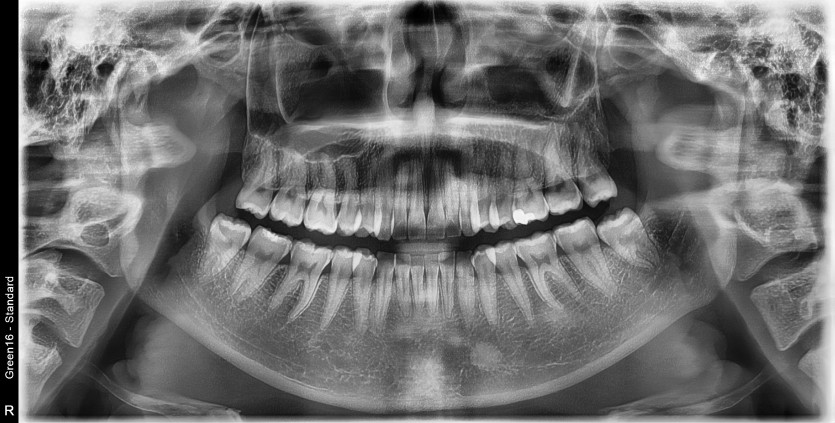

#28,38 사랑니 발치

구강외과 전문의가 당일 발치했습니다.